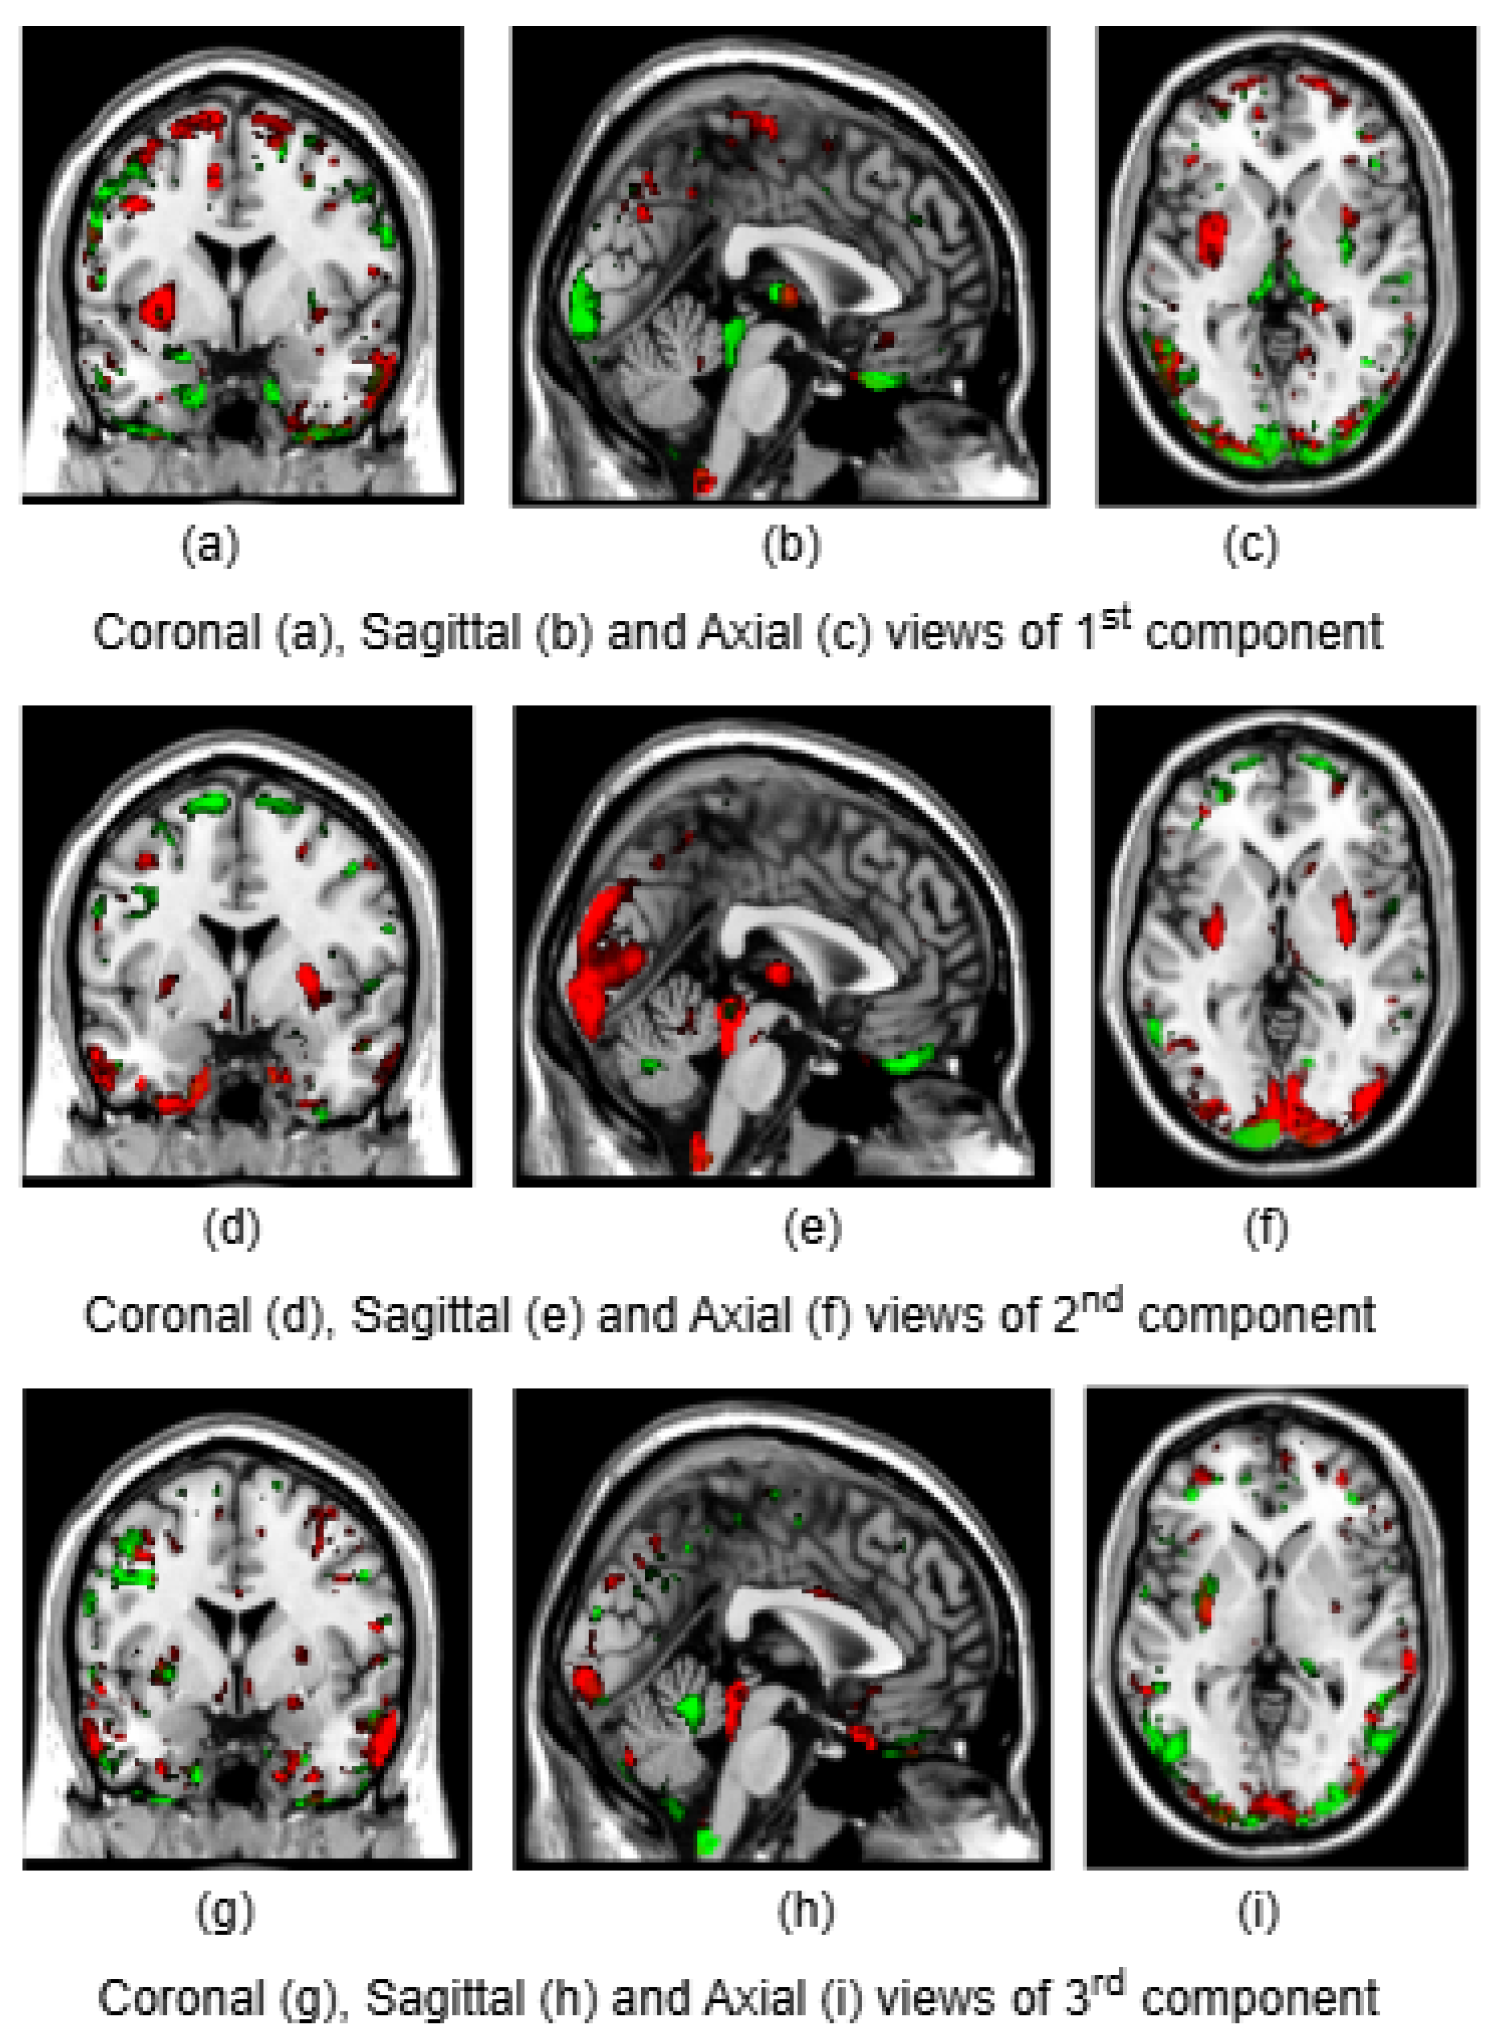

To illustrate the brain regions, the top PCs of the first three significantly correlated GM and FA components were plotted for both CCA and DCCAE results. To plot the brain regions, the CCA/DCCAE components were traced back to PCA components using the weight matrix of CCA/DCCAE, and the top PCA components were then mapped to the brain regions.

Figure 1 and Figure 2 depict GM and FA regions for CCA respectively, while Figure 3 and Figure 4 portray GM and FA regions for DCCAE respectively, with green indicating positively correlated GM and FA regions and red indicating negatively correlated regions. The GM regions identified by the first component of CCA include the middle temporal gyrus, precentral gyrus, middle frontal gyrus, superior frontal gyrus, and sub-gyral regions. The second component highlights the cuneus, middle occipital gyrus, superior frontal gyrus, lingual gyrus, and superior temporal gyrus. The third component encompasses the superior frontal gyrus, middle frontal gyrus, cuneus, superior temporal gyrus, middle occipital gyrus, and thalamus. Similarly, the first component of DCCAE reveals cuneus, middle temporal gyrus, precentral gyrus, middle frontal gyrus, rectal gyrus, superior temporal gyrus, inferior parietal lobule, middle frontal gyrus and superior frontal gyrus. The second component identifies cuneus, middle occipital gyrus, superior frontal gyrus, middle frontal gyrus, sub-gyral, postcentral gyrus, precuneus and middle temporal gyrus. The third component includes middle temporal gyrus, precentral gyrus, cuneus, lingual gyrus, middle occipital gyrus, inferior frontal gyrus, postcentral gyrus and inferior parietal lobule.

Similarly, the FA regions identified by the first component of CCA include corticospinal tract, anterior thalamic radiation and forceps minor. The second component highlights corticospinal tract, anterior thalamic radiation, forceps minor and inferior longitudinal fasciculus. The third component recognizes anterior thalamic radiation, forceps minor, inferior longitudinal fasciculus and inferior fronto-occipital fasciculus. Likewise, the first component of DCCAE point out anterior thalamic radiation, forceps minor, inferior longitudinal fasciculus, corticospinal tract and inferior fronto-occipital fasciculus. The second component spot forceps minor, inferior longitudinal fasciculus, corticospinal tract and anterior thalamic radiation. The third component includes corticospinal tract, anterior thalamic radiation and forceps minor.

Figure 3. Coronal, sagittal and axial views of first, second, and third components of GM identified by DCCAE

When examining the direct similarity between components of CCA and DCCAE, we found out that most of the CCA components (for both GM and FA ) have high and significant correlations (shown in Tables 3 and 4) with some of the DCCAE components. For example, CCA GM component 1 is significantly and negatively correlated to DCCAE GM components 1 and 2, and positively correlated to DCCAE GM component 3. Similar results were observed for FA components where CCA FA component 1 was linked to DCCAE FA components 1 and 2 negatively and component 3 positively. The negative correlation observed in Tables 3 and 4 does not indicate a fundamental contradiction in the relationship between GM and FA features. Instead, it suggests that for the same brain region, CCA encodes a change in one direction (increase or decrease), while DCCAE encodes it in the opposite direction. However, the underlying GM-FA association remains consistent across both models. This difference in sign can be further illustrated in Figure 1 and 3, where the first components from CCA and DCCAE show similar spatial patterns, particularly in the posterior occipital region but the color representation differs indicating an increase in one model and a decrease in the other.

We also examined the contributing brain regions of components that shared the same brain regions. The top PCs of the CCA and DCCAE components highlighted common regions for GM and FA. The first CCA component correlates with the first, second and third DCCAE components. The brain regions of the first CCA components which include middle temporal gyrus, precentral gyrus, middle frontal gyrus, superior temporal gyrus and sub-gyral while DCCAE’s first component identified middle temporal gyrus, middle frontal gyrus, and sub-gyrus, DCCAE’s second component identified middle temporal gyrus and middle forntal gyrus, DCCAE’s third component identified superior temporal gyrus and precentral gyrus. Similarly, common FA regions were also observed for CCA FA component and DCCAE FA components. The brain regions of the first CCA components include corticospinal tract, anterior thalamic radiation and forceps minor, and DCCAE’s first, second and third components identified the brain regions pointed by the first component of CCA.